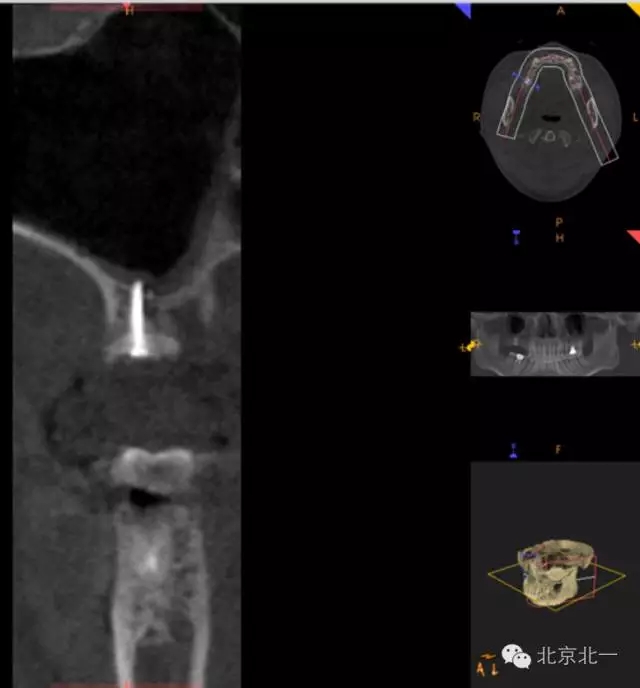

圖三:骨高度3mm.

CBCT顯示,骨寬度可,骨高度不足,月3mm。頜間距離增大。

圖十八:手術(shù)前CBCT